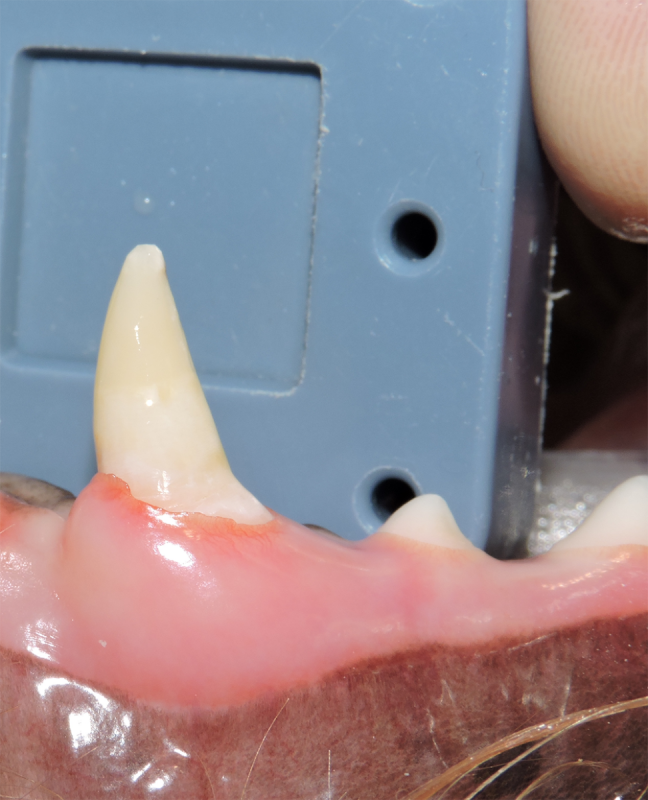

Tooth resorption is a disease process where the body begins to break down the adult tooth. It is widely known to occur in cats but can also occur in dogs. In cats these lesions are thought to be inflammatory, while in dogs they can be more of a replacement resorption process. These lesions can be very painful and should be treated, generally with extraction depending on the type of resorption that is occurring. The disease can be progressive and affect many teeth over several years. It is important to have regular checkups and yearly dental cleanings to monitor for these lesions.